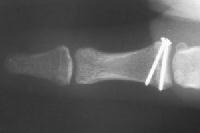

Injuries associated with a large avulsion fracture can be repaired with one or two micro screws, as was done here: